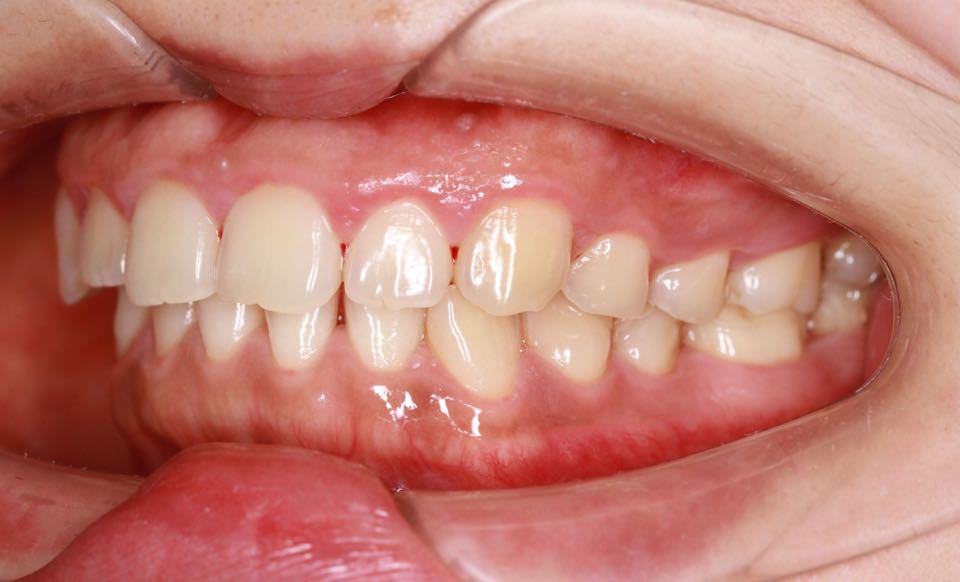

矫正前口内照:

口内:恒牙列,牙列拥挤(中度)。上下颌牙弓呈方圆型。左右对称。右侧磨牙近中性关系,左侧磨牙近中关系,右侧尖牙远中关系,左侧尖牙远牙中性关系。上颌中线偏右2mm,下中性居中。